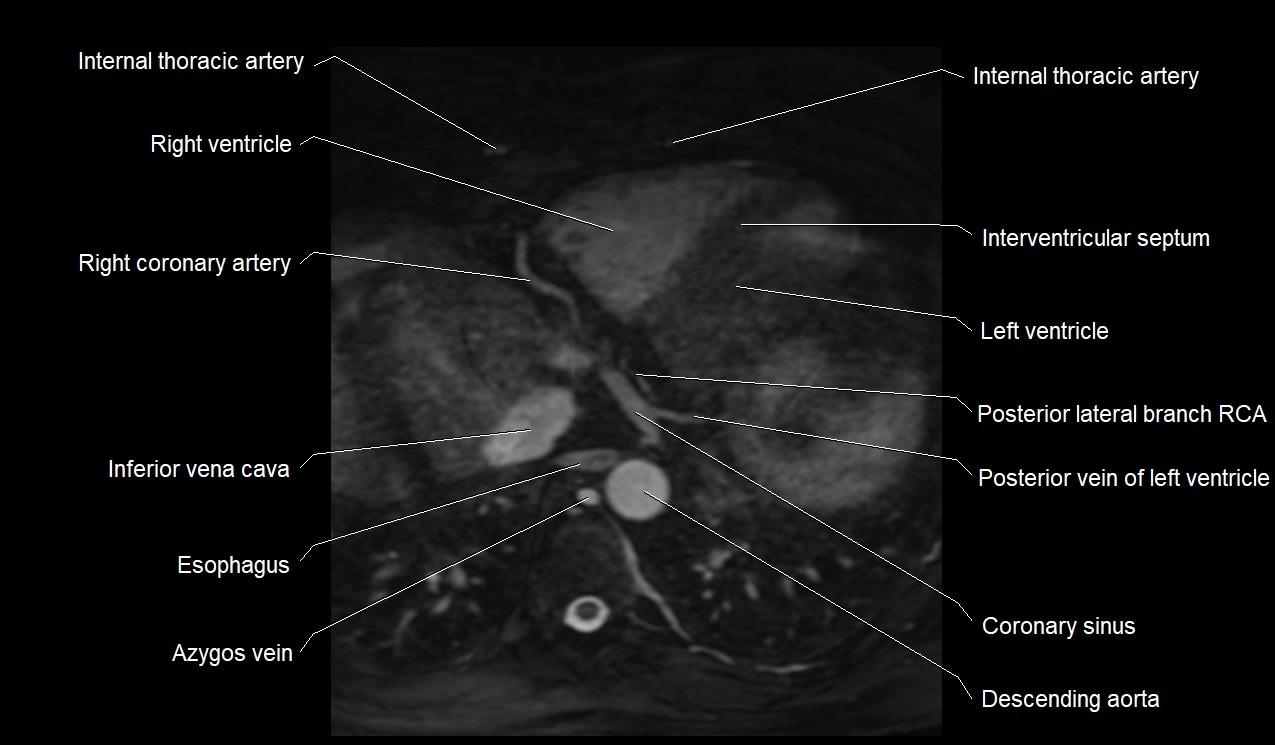

MRI image